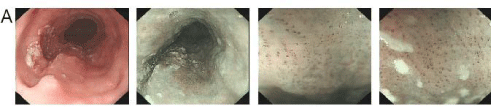

A 67-year-old man complained of intermittent upper abdominal distension. Gastroscopy showed that high-grade intraepithelial neoplasia of esophageal squamous growth 29cm from the incisors (Figure A), He underwent the ESD for the esophagus lesion (Figure B), pathologic proved that squamous cell carcinoma invaded the submucosa with a depth of more than 750 um. Computed tomogram (CT) of Chest and abdomen showed thickening of the middle esophageal wall, considering esophageal cancer, lesions between the stomach at the lower esophagus and cardia, and the possibility of stromal tumors or leiomyomas (Figure C, D). Barium meal of upper digestive tract asserted equally the rigid and filling defect of middle thoracic esophageal tube wall was observed, and no obvious niche and filling defect was found in gastric wall (Figure E). Because of the attack of cerebral infarction, the patient rejected the surgery and refuse to the chemotherapy in the followup planning. He underwent radiation therapy only for the primary esophagus. A 3D-CRT plan was designed, the planning target volume (PTV) was 60Gy in 30 fractions. After the recovery of the radiotherapy, and patients received the resection of partial gastrectomy plus small curvature lymphadenectomy. The operation showing that the tumors were located on the lesser curved side of the stomach, with a diameter of about 3cm, and there was a swollen lymph node with a diameter of about 2.5cm. Postoperative pathology showed moderately differentiated squamous cell carcinoma, local cancer tissue adjacent to the incision margin, considered as esophageal cancer proliferation, the left gastric lymph node also showed moderately differentiated squamous cell carcinoma. A follow-up study was performed 2 months after the surgery, no recurrence and metastasis was found.

Figure C, D: CT of Chest and abdomen: The middle esophagus was obviously thicker, and the lesions of the stomach with the largest diameter of about 3 cm were found in the lower esophagus and cardia, showed uneven density enhancement.